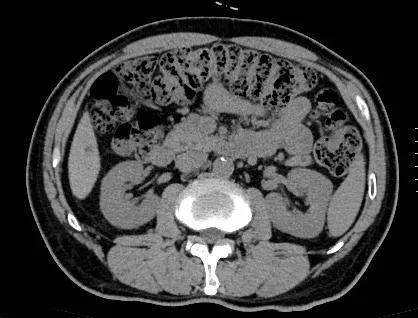

傅传刚教授随后为王先生安排了肠镜:结肠镜插入至肝区,结肠冗长迂曲,进镜困难,所见横结肠,降结肠,乙状结肠及直肠粘膜光滑,见色素沉着,余未见异常。诊断:中度结肠黑变病 结肠冗长迂曲。

傅传刚教授是全国著名肛肠疾病专家,擅长于肛肠疾病的诊断、治疗和基础研究,其中包括慢性顽固性便秘。傅教授认为,对于这样一例老年性帕金森顽固性便秘患者服药,当非手术治疗无效时,需要安排手术治疗,而王先生基础疾病较多,手术风险较大,手术方式需要慎重。于是傅传刚教授组织多学科讨论,请神经内科各相关科室会诊,采用“3D腹腔镜、白色无血、极致微创、精细精准、腹部无切口”先进技术。次全切除同时行升-直肠吻合术,术后便秘症状改善率可达90%。能有效减少术后肛门*禁失**的发生率,提高患者的生活质量。

排除手术禁忌症后,傅传刚教授和鲁兵教授于10.26日共同为王先生实施全腹腔镜结肠次全切除术升结肠直肠端端吻合术复杂粘连松解术盆底重建术